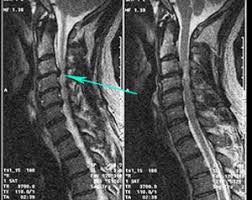

A vizsgálat után kapott CD-re ilyen minőségű képeket rögzít a gép.

A számítógépen mozgatható, léptethető, forgatható a kép, különböző rétegekben és magasságokban. (Ezt jól lehetett látni a videók végén.) A különböző szögekből készült felvételeken alaposan áttekinthető a problémás terület.

Itt például a nyaki szakasz látszik. A nyilnál látható, hogy a gerincvelőt nyomja a kitüremkedett porckorong.